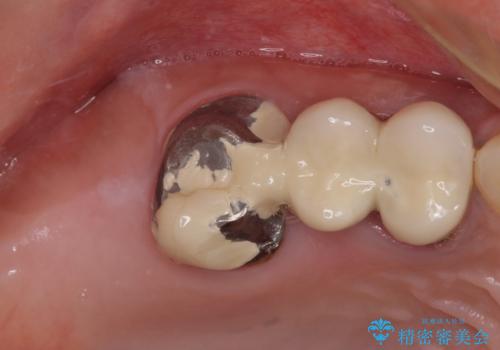

レントゲン写真などで診査した結果、奥歯の銀歯の下にはむし歯が多く存在し、右上の奥歯は歯根が破折していました。

破折した歯を抜去し、インプラントによる補綴を行うこととしました。

銀歯の下のむし歯については、優先度の高い方からセラミッククラウンなどで治療していくこととしました。